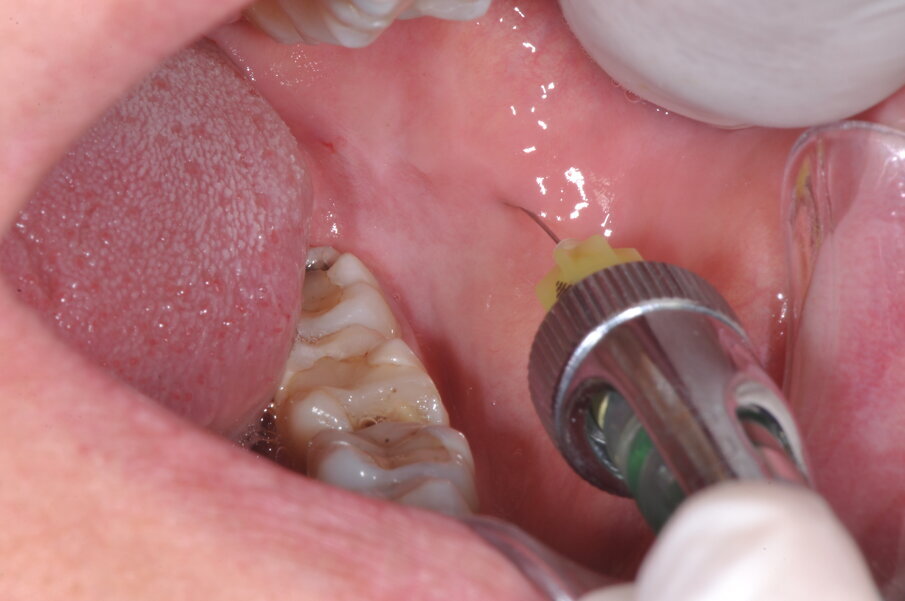

È quindi opportuno che un anestetico topico venga preliminarmente usato per rendere la fase di iniezione la meno sgradevole possibile, che l’iniezione venga eseguita applicando la giusta pressione, in modo da non sovradistendere i tessuti molli (una delle causa di dolore) e che sia fatta nel corretto sito anatomico (Figg. 1, 2). Il tempo di iniezione raccomandato è 1 ml/minuto. Tuttavia, l’84% dei dentisti inietta 1,8 ml in 20 secondi o meno. Inoltre la molecola opportuna per l’intervento programmato dovrà essere selezionata in base alla durata attesa della sua azione e, quindi, della sua efficacia, prestando attenzione anche alla quantità di vasocostrittore presente e alla condizione di salute generale del paziente.

Fig. 1 - Anestesia del nervo inferiore alveolare.